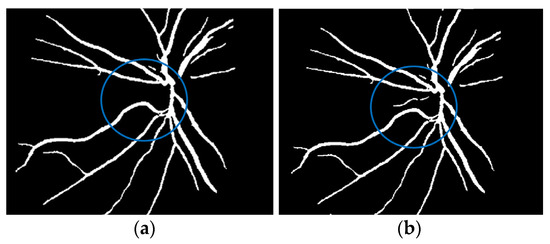

where f(vessel, background) corresponds to the input image, g(vessel, background) denotes the binary pixel after thresholding, and 128 is the optimal value to classify the histograms between the two classes. Any pixel (vessel, background) in the image at which f(vessel, background) ≥ 128 is extracted as a vessel pixel; otherwise, the pixel is regarded as a background point or a non-vessel pixel. The extraction result is displayed in Figure 8, where pixels with intensity values greater than 128 (retinal blood-vessel pixels) are shown in white against a background of black. As shown on the left side of Figure 8a, there are a few false extractions; they segment the actual retinal blood vessels (white pixel) as the background (black pixel). The Dilatation-Based Function is added to optimal thresholding functions to reduce the false negative value (see Figure 8b).

Figure 8.

Comparison of the extraction results with WKFCM false extraction and adding morphological dilation operator: (a) intensity thresholding with a loose extraction using WKFCM, (b) intensity thresholding using the proposed Dilatation-Based Function technique (demonstrated within the blue line).